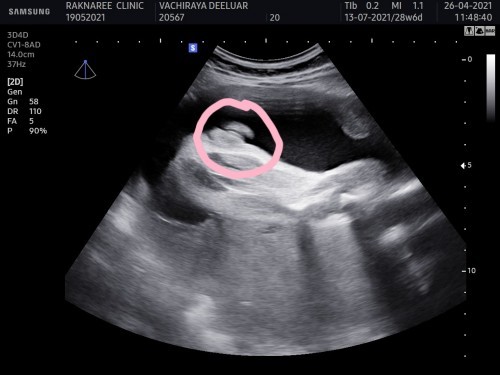

แบบนี้ผญ100%ไหมคะ🤣🤣

ถ้ามองด้วยตาก็เป็นกลีบๆ คุณหมอว่ายังบ้างคเแม่ คือเด็กผญ.จะดูยากกว่าเด็กผช. บางทีมีหลอกด้วย ซาวด์ไปซาวด์มาจู๋โผล่ก็มีค่ะ😁